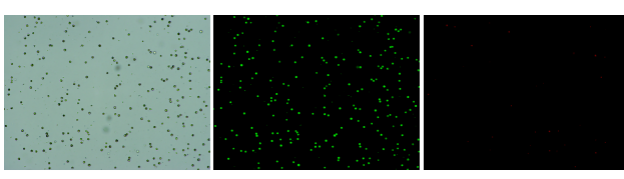

實驗結(jié)果

人肝癌樣本,懸液背景干凈,活性91.69%,結(jié)團(tuán)率6%